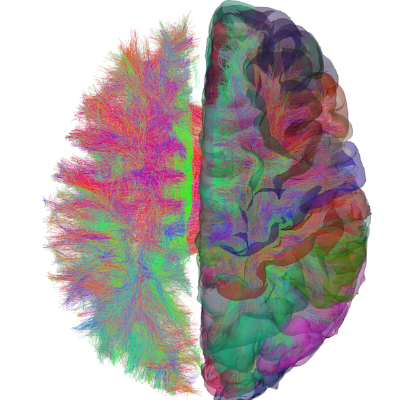

After uploading MRI data to the supercomputer, the pipeline runs the three containers

The TVB Processing Pipeline takes multimodal MRI data sets (anatomical, functional and diffusion-weighted MRI) as input and generates SCs, region-average fMRI time series, FCs, brain surfaces, electrode positions, lead field matrices, and atlas parcellations as output. The pipeline performs preprocessing and distortion-correction on MRI data as well as white matter fiber bundle tractography on diffusion data. Outputs are formatted according to two data standards: a TVB-ready data set that can be directly used to simulate brain network models and the same output in BIDS format.